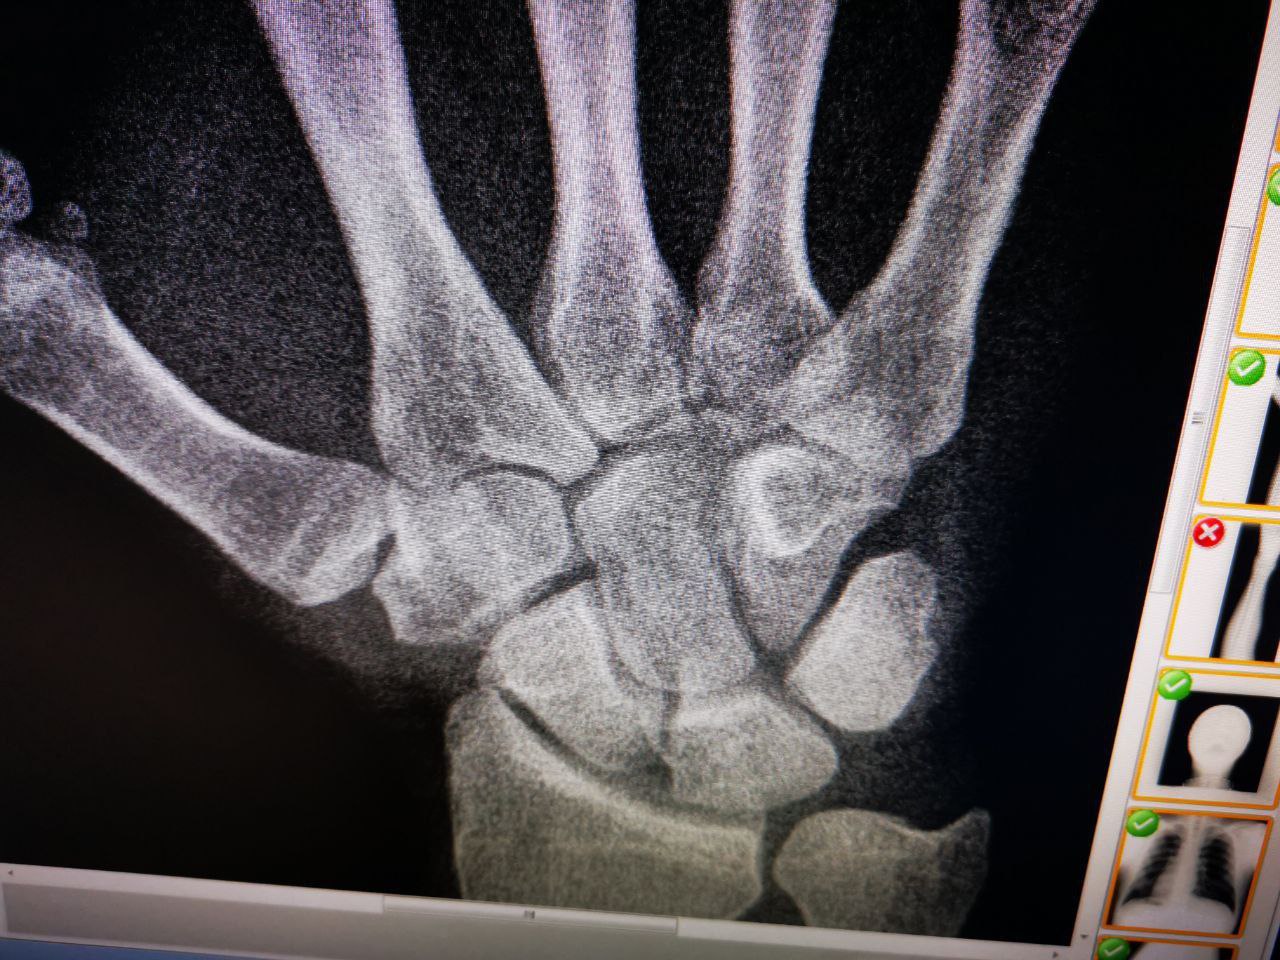

Пациент 38 лет, боли в кисти

Что может быть?

Перелом основание V пястной фаланге без смещением к/о.